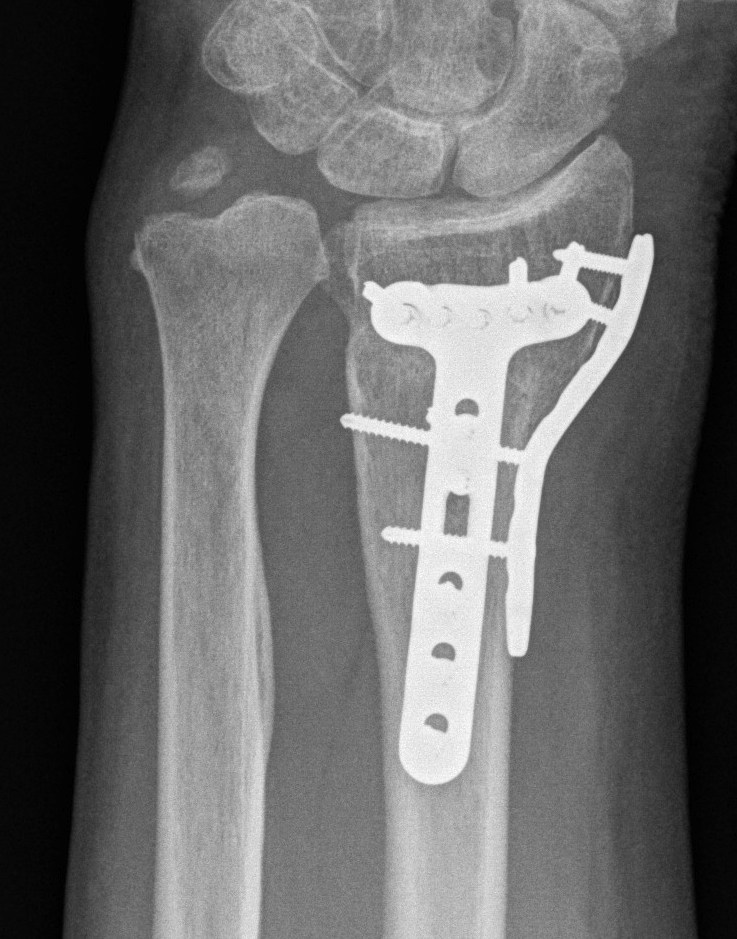

Surgical options

Volar locking plates

Distal Radius Fracture K wires APplateex fixbridge plate